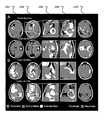

FIGS. 3A, 3B, 3C and 3D show example of quantitative comparisons of results obtained by the disclosed method and results obtained by human operators.

FIGS. 4A, 4B, 4C, 4D and 4E show example of effects of the choice of the sample set for the segmentation.

FIGS. 3A and 3B show examples of quantitative comparisons of results obtained by the disclosed method and results obtained by human operators. Quantitative comparison between IPVL-defined volumes and operator-derived volumes compared relative to inter-operator comparisons. (A) Dice coefficient (DICE) comparisons for IPVL-defined and operator-defined CE volumes. DICE scores were calculated as previously described comparing CE volumes generated by IPVL,operator1, andoperator2. (B) DICE score comparisons for IPVL-defined and operator-defined FH volumes. DICE were calculated comparing FH volumes generated by IPVL,operator1, andoperator2.

FIGS. 3C and 3D show examples of quantitative comparisons of results obtained by the disclosed method and results obtained by human operators. Quantitative comparison between IPVL-defined volumes and operator-derived volumes compared relative to inter-operator comparisons.FIG. 3C andFIG. 3D respectively show DICE score comparisons for IPVL defined and operator defined FH volumes. DICE scores were calculated by comparing FH volumes generated by IPVL,operator1 andoperator2.

Examples from four subjects which represented the CE and FH volumes with the highest and lowest DICE scores relative tooperator1 are shown inFIG. 2. Corresponding FH segmentations for CE and CE segmentations for FH are included to show that segmentation success for one feature is not necessarily correlated with segmentation success for corresponding features. Analysis showed no statistical difference between operator-derived volumes sooperator1 was selected as the basis for image comparison (p=0.72 for CE, and p=0.10 for FH).

FIG. 2 demonstrates that the algorithm generates highly analogous CE and FH volumes relative to those derived manually. IPVL CE volumes were statistically indistinguishable from volumes generated by expert operators across all subjects (p=0.93). DICE scores, for automated CE volumes, relative tooperator1 andoperator2 averaged 0.923 and 0.921, respectively. These DICE scores were highly comparable to those obtained from inter-operator analysis (average of 0.923,FIG. 3A).

For automated FH volumes, the DICE scores relative tooperator1 andoperator2 averaged 0.851 and 0.815 respectively. DICE scores obtained from inter-operator analysis averaged 0.905 (FIG. 3B). Analysis revealed that FH volumes were slightly lower than inter-operator comparison (p=0.04). We observed that FH DICE scores were poorer than CE DICE scores for both the inter-operator and the operator-algorithm comparisons. Overall, the DICE scores for both CE and FLAIR achieved through our algorithm were improved or similar relative to those previously reported.

FIGS. 4A, 4B, 4C, 4D and 4E show examples of effects of the choice of the sample set for the segmentation. (FIG. 4A) Select image sequences (such as T1w) were removed prior to IPVL CE segmentation. The image sequence(s) available for IPVL was indicated as +. DICE score was calculated for the resultant CE segmentation relative to operator1-defined CE volume. The distribution of DICE across all subjects as a result of image sequence removal was shown as a box-plot. (FIG. 4B) Select image sequences were removed prior to IPVL FH segmentation. The image sequence(s) available for IPVL was indicated as +. DICE was calculated for the resultant FH segmentation relative tooperator1 defined FH. The distribution of DICE across all subjects as a result of image sequence removal was shown as a box-plot. (FIG. 4C) Box plot demonstrating the range DICE score for IPVL segmented CE volume relative to operator-defined CE volume per patient for all image combinations tested. (FIG. 4D) Box plot demonstrating the range DICE score for IPVL segmented FH relative to operator-defined FH per patient for all image combinations tested. (FIG. 4E) Box plot demonstrating the range DICE score for IPVL segmented CE volume relative to operator-defined CE volume per patient when only T1w and FLAIR source images were used for IPVL segmentation.

For CE volume segmentation, removal of T1w and T2 images did not significantly affect performance. The DICE scores obtained when comparing volumes delineated using only T1wCE and FLAIR were comparable to those obtained when all 4 imaging sequences were processed by our algorithm (FIG. 4A). Similarly, FH volume segmentation was minimally impacted by image reduction, and DICE scores using all 4 imaging sequences were comparable to those obtained when using only T1wCE and FLAIR (FIG. 4B).

To further characterize the impact of reducing the number of image sequences on the performance of CE and FH segmentation, we plotted the range of DICE scores that resulted from removing one or more image series for each subject. For most subjects, removing images minimally impacted DICE scores, meaning that the quality of volume segmentation was not significantly altered (FIG. 4C for CE,FIG. 4D for FH). For FH segmentation, removal of T2w and T1w images did not significantly affect DICE scores relative to Operator1 (FIG. 4D for FH).

Only two subjects, TCGA-02-0068 and TCGA-06-0164, had increased vessel contamination of the CE volume when FLAIR images were removed during image reduction analysis. CE segmentation for image combinations which contained at least a FLAIR and T1wCE image were highly comparable across all subjects (FIG. 4E). While adequate CE segmentation required only T1wCE for the majority of cases, FLAIR images improved CE and BV discrimination and may be required for segmentation in a subset of subjects. Surprisingly, CE segmentation for T1wCE and FLAIR alone was nearly identical to CE segmentation results which utilized all available imaging series. These results suggest that our algorithm requires only T1wCE and FLAIR images for robust volume segmentation of both tumor-associated CE and FH volume, and that additional imaging series do not contribute significantly to the segmentation results.